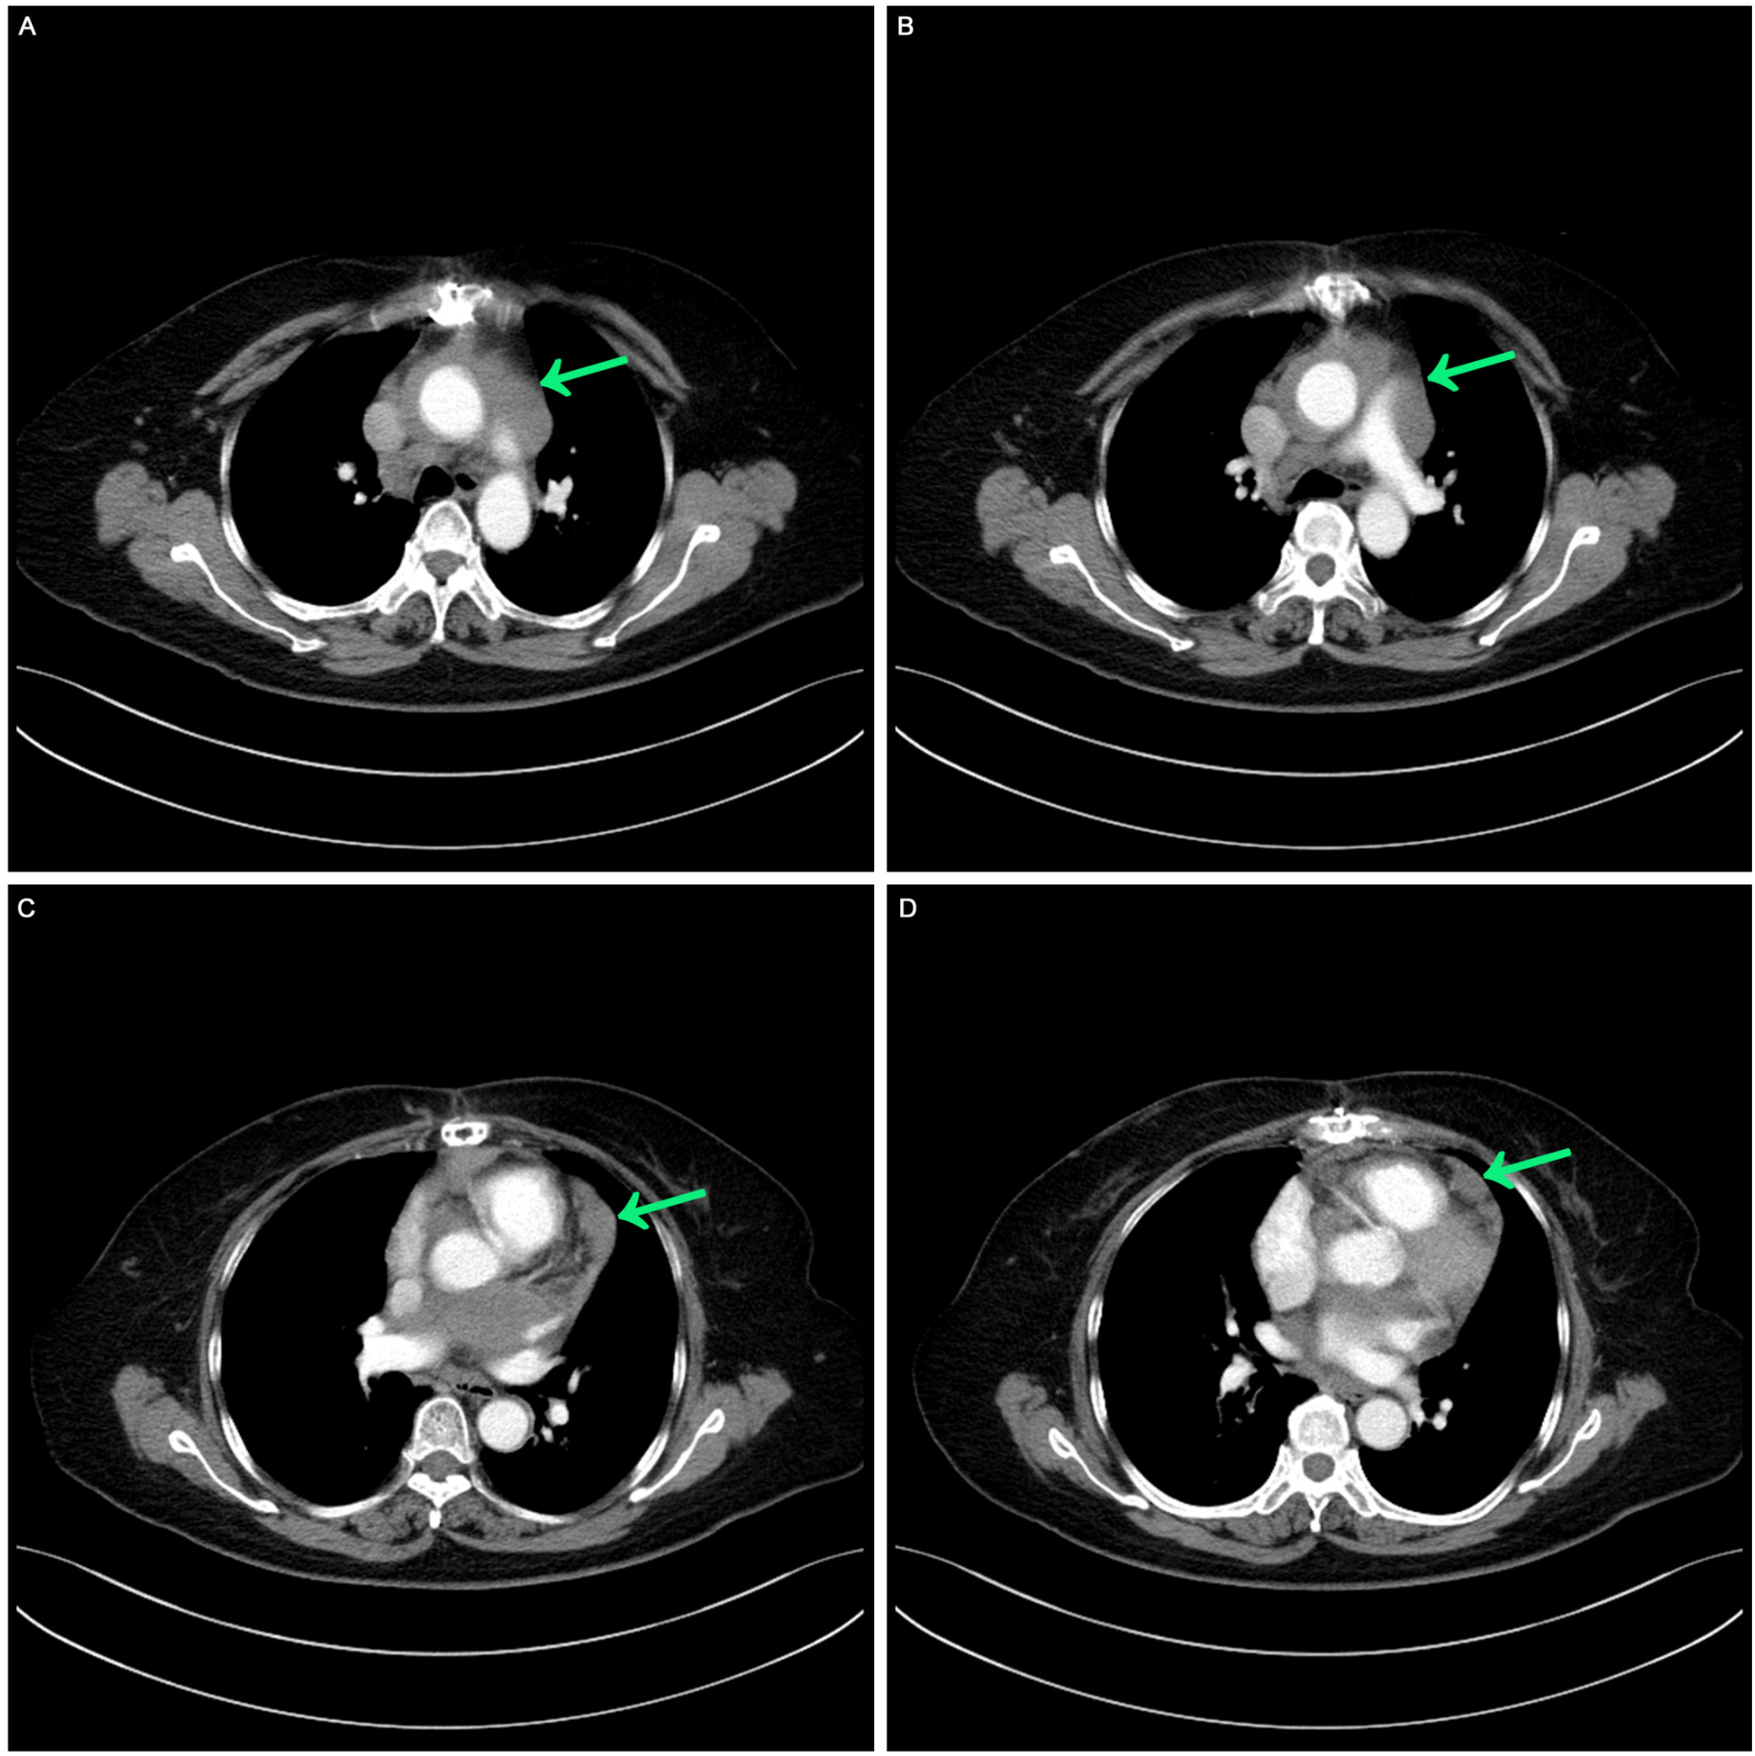

Before systemic treatment, the patient's body weight and length were 70 kg and 163 cm, respectively, and her blood pressure, heart rate, and respiratory rate were 139/84 mmHg, 106 beats/min, and 20 breaths/min, respectively. The physical examination was notable for swelling of the right limb and jugular vein elevation. The initial laboratory analysis revealed that the white blood cell count was 10,910 cells/mm3, the BUN/creatinine ratio was 24.4, the high sensitivity troponin I level (hstroponin I) was <0.02 ng/ml, BNP was 66.9 pg/ml, and blood CA125 level was 53.36 u/ml, non-small cell antigen was 55.32 ng/ml, and NSE was 36.03 ng/ml. Electrocardiography showed sinus tachycardia without abnormal T waves or ST segment changes. Echocardiography revealed a solid hypoechoic area in the pericardial cavity above the left atrium and anterior to the left pulmonary artery, measuring approximately 13 × 3 cm, with an unclear border, irregular shape, and no evident blood flow on color Doppler flow imaging. Due to the patient's inability to lie flat, no chest CT or heart MR signs were obtained before chemotherapy. We discussed the following therapeutic regimen. The treatment plan involved chemotherapy combined with immunotherapy administered from September 07, 2023, to January 19, 2024, comprising 6 cycles. The specific drug regimen consisted of pemetrexed 500 mg/m2, carboplatin AUC = 5, and pembrolizumab 200 mg, repeated every 3 weeks. During the third cycle of chemotherapy, sequential pericardial occupying lesion radiotherapy was conducted with a dose of 50Gy/25Fx. Following the first cycle of chemotherapy, cancer pain subsided, leading to the discontinuation of painkillers and enabling the patient to sleep semi-reclined with elevated pillows at night. A reassessment before the third cycle of chemotherapy indicated regression of the pericardial mass (Figure 2). After completing first-line treatment, a follow-up evaluation two months later revealed further regression of the pericardial mass (Figure 3).

Figure 2

Postoperative contrast-enhanced CT: mild thickening of the pericardium before the third cycle of chemotherapy. (A,B) Computed tomography image showed masses around the aorta and pulmonary arteries. (C,D) Computed tomography image shows mild thickening of the pericardium.